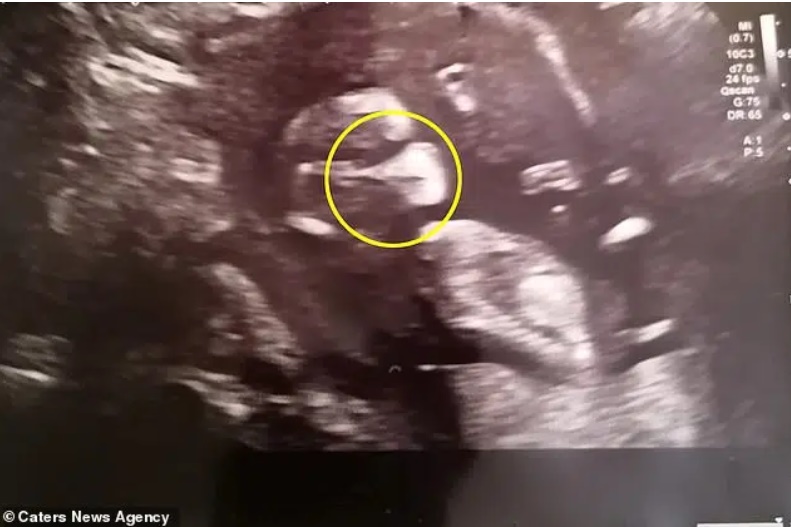

Hình ảnh siêu âm thai nhi con gái của Samantha Spicer (34 tuổi, đến từ Rushden, Northamptonshire, Anh).

"Những khoảng sáng trên màn hình siêu âm đã tạo ra hình ảnh giống như một chiếc khẩu trang trên khuôn mặt của con gái tôi. Ngay khi siêu âm, các bác sĩ ở đây và tôi đã cười lớn. Hình ảnh đó thật sự rõ ràng.

Chúng tôi còn thầm đoán rằng, liệu có phải con tôi đã biết trước rằng mẹ của nó bị nhiễm COVID-19 nên đã chuẩn bị sẵn sàng để đối phó với dịch bệnh từ trong bụng mẹ hay không.", Samantha nhớ lại.